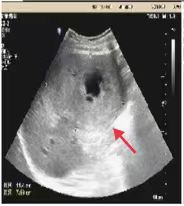

08、**女士,37岁

于2023年11月7日在邢台仁泰体检部体检,腹部彩超检查提示:腹腔内约7.4*6.3cm囊实性混合回声,2023年11月7日电话通知,建议客户到三甲医院进一步检查。2023年11月14日跟踪回访,客户已到邢台市人民医院住院准备手术。